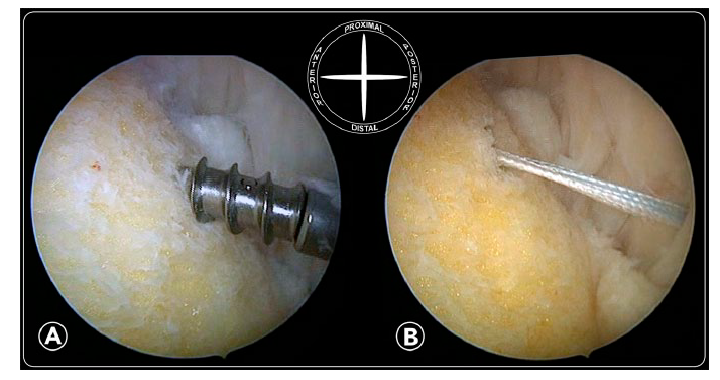

关节镜下手术可以减少并发症、缩短住院时间,病人满意度高,可以在门诊完成。关节镜下手术和中间跟腱劈开入路在手术效果和病人满意度方面无明显差异。

尸体试验:关节镜手术和开放手术对内侧跟腱、跖肌腱和神经的损伤概率无统计学意义。

尸体试验:开放手术比关节镜手术切除跟骨结节更多,清理更完全。

关节镜下锚钉跟腱加强